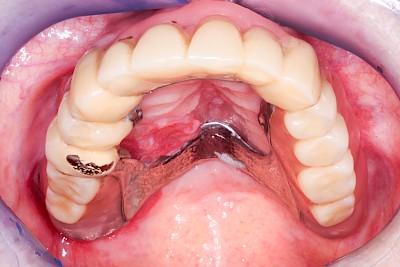

Schlechter Halt & schlechte Passung

Immer wieder kommt es vor, dass Zahnprothesen schlecht passen und/oder schlecht halten. Eine schlechte Prothesenpassung zeigt sich daran, dass die Prothese stark "schaukelt", wenn man auf die Zahnreihen drückt. In erster Linie ist dies auf den Knochenschwund, die sogenannte Atrophie, zurückzuführen. Knochenschwund ist individuell sehr unterschiedlich ausgeprägt. Genetische Veranlagung aber auch intensives Tragen der Zahnprothese sowie ständiges Knirschen und Pressen können Einflussfaktoren sein.

Hält eine Teilprothese kann es auch sein, dass das Verbindungselement defekt oder verlorengegangen ist. In diesen Fällen ist zu prüfen, ob eine Klammer abgebrochen oder ein Verbindungselement wie z. B. eine Krone fehlt. Ist dies der Fall muss ein Zahnarzt gerufen werden.

Bei manchen Prothesen verschlechtert sich der Halt, weil die Haltewirkung der Verbindung zwischen der Prothese und den Restzähnen oder Implantaten nachlässt. Nicht selten sind auch einzelne Verbindungs- bzw. Verankerungselemente einfach "verloren" gegangen (verschluckt, ausgespuckt und ganz selten aspiriert!). Manchmal stecken die Kronen, die die Prothese mit den Restzähnen verbinden, in der herausnehmbaren Prothese. In Ausnahmefällen sind die Ankerzähne oder Implantate selbst nicht mehr im Knochen fest verankert und gehen mit der Prothese insgesamt raus. In allen diesen Fällen sollte der Zahnarzt gerufen werden.